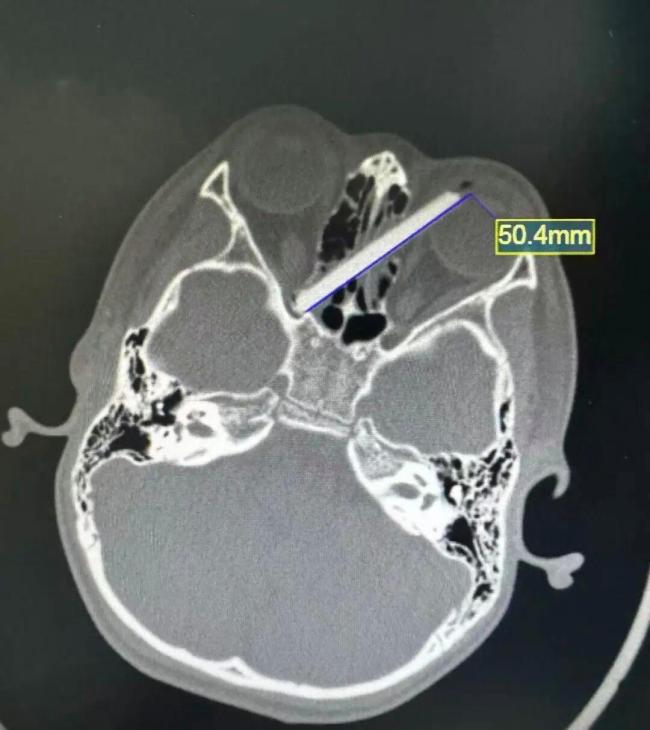

医生检查后发现,孩子的眼睛表面没有看到插着的筷子,只有左眼眼白处有一个小黑点。据孩子父母描述,孩子当时摔了一跤,手中的筷子少了一截。他们四处寻找那截失踪的筷子未果,担心筷子插进了孩子的眼睛。CT检查结果显示,筷子确实插进了孩子的左眼,贯穿双侧鼻窦,并且另一端深深嵌入右眼视神经管附近。

筷子紧贴着孩子的左眼球壁,稍有偏差就可能导致左眼球破裂;而另一端则紧紧抵住右眼的视神经管,一旦视神经受损,孩子随时面临失明的风险。除了视力问题,眼眶周围和鼻窦内血管密布,且紧邻大脑,如果不及时手术取出筷子,很可能引发血管破裂、大出血甚至颅内感染。因此,医生立即安排孩子进行手术。